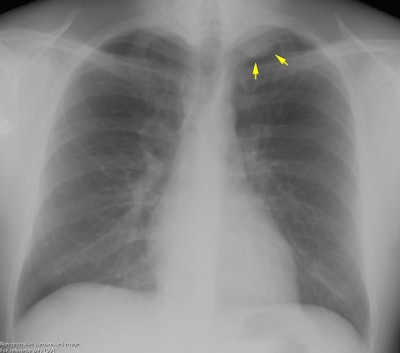

The patient shown below was asymptomatic and had his chest radiograph performed as part of a routine physical exam. The chest radiograph demonstrated a left apical soft tissue density mass (yellow arrows) with smooth inferior margins. A CT scan was performed (see below).